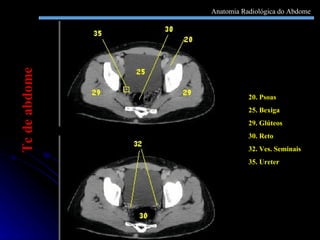

20. Psoas  25. Bexiga 29. Glúteos 30. Reto 32. Ves. Seminais 35. Ureter Tc de abdome Anatomia Radiológica do Abdome